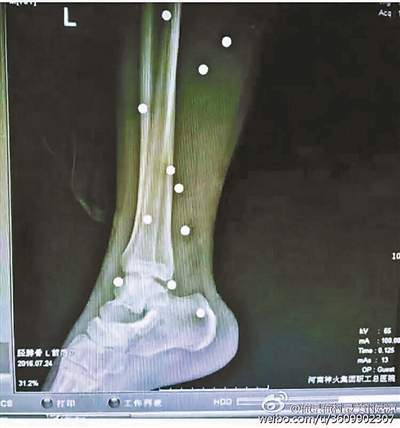

傷者體內取出的鋼珠

爆炸導致鋼珠遍布傷者身體各處

黃明的伯伯對北青報記者表示,由于黃明直接踩到了爆炸物,所以傷情最為嚴重,“他的腿被炸斷,身體內被炸進了40多顆鋼珠。手術后已經從體內取出29顆鋼珠,還有十多顆鋼珠沒有取出來?!备鶕S明的入院記錄,他全身有多處爆炸傷,且全身多處異物存留。